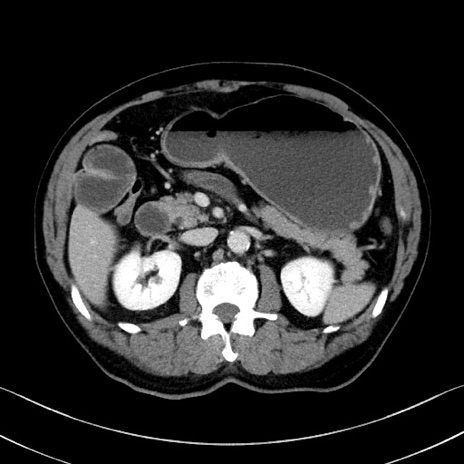

症例35(横断像)

【症例】70歳代 男性

【主訴】腹部膨満、嘔吐

【現病歴】昨日より腹部膨満感出現。本日増悪し、仙痛出現。嘔吐あり、受診。

【既往歴】糖尿病、胆摘後

【身体所見】BP 149/80mmHg、HR 74/min、BT 35.9℃、腹部:膨満、軟、圧痛なし。腸雑音減弱あり。上腹部正中切開瘢痕あり。

【データ】WBC 13500、CRP 1.72